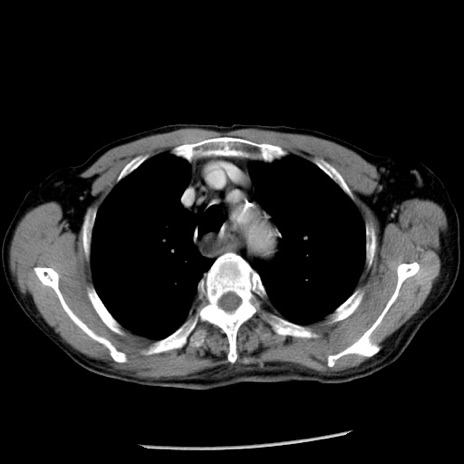

症例26(横断像)

【症例】80歳代男性

【主訴】嘔吐

【現病歴】昨晩2回嘔吐あり、今朝になっても嘔吐あり。来院。

【既往歴】胃潰瘍

【身体所見】意識清明、BT 37.6℃、BP 166/95mmHg、HR 100bpm、SpO2 97%、腹部:平坦・軟、腸蠕動音聴取良好、圧痛なし。

【データ】WBC 21900、CRP 1.46